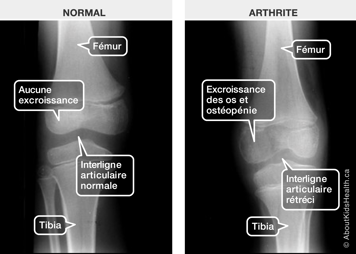

Un rayon X est un type de radiation qui passe à travers le corps. Un rayon X laisse une empreinte des os sur une photographie. Cet examen donne au médecin de l’information sur la grosseur, la forme et la position des os et de certains organes. Cette information peut aider à diagnostiquer une maladie. Cet examen est aussi appelé une radiographie. La quantité de radiation d’un rayon X est petite. Une radiographie seule ne peut pas diagnostiquer l'arthrite.

Habituellement, au début de la maladie, les rayons X sont normaux et, par conséquent, ils ne servent pas au diagnostic d'une AIJ. Les rayons X servent souvent à écarter d’autres problèmes. Ils peuvent aussi servir à s’assurer que l’AIJ n’a pas causé des dommages prématurés aux os.